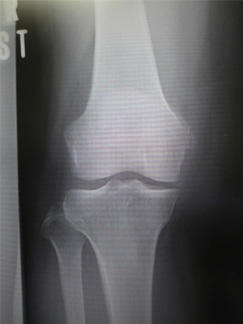

では写らないのになぜ減っていると分かるのでしょう?それはレントゲン写真において関節裂隙(かんせつれつげき)の狭少化や骨の変形が確認できるからです。軟骨が残っている場合、大腿骨と脛骨の隙間は開いて見えます。しかし軟骨が減ってきた場合、次第にその隙間は狭くなり最終的には消失してしまいます。また骨もストレスを受ける事で硬くなったり変形したりしてきます。レントゲンで変形性膝関節症を確認したい時には立って写真を撮った方が色々な情報が得られます。変形性膝関節症は女性が4:1の割合で女性に多い疾患です。

正常膝

変形性膝関節症